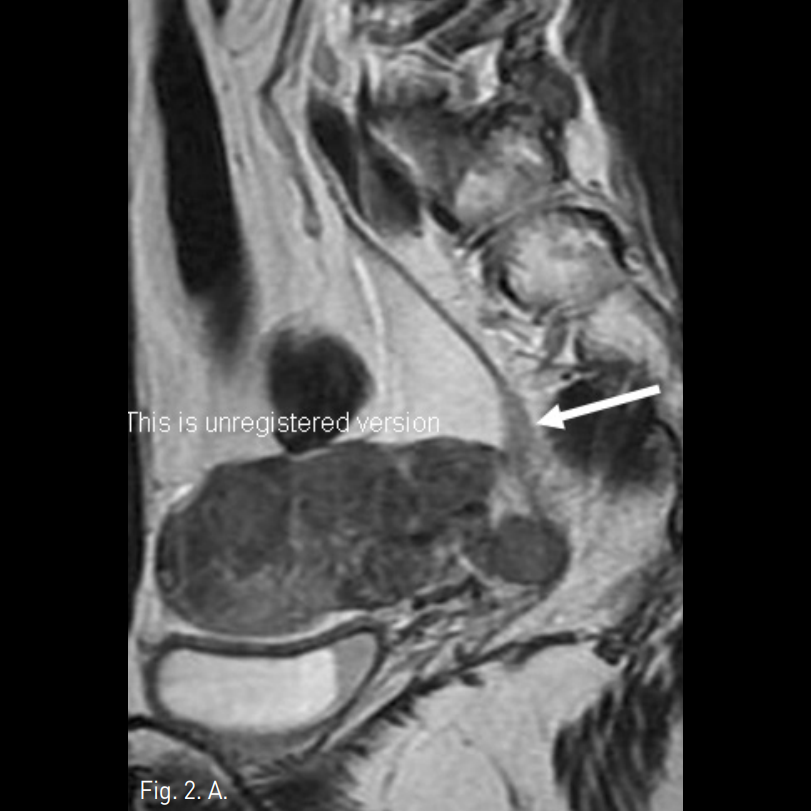

Fig. 2

A, B, C. T2 weighted sagittal MR images and Gadolinium enhanced T1 weighted image demonstrate the mass is growing along the internal iliac vein superiorly (arrows in A, B and C).